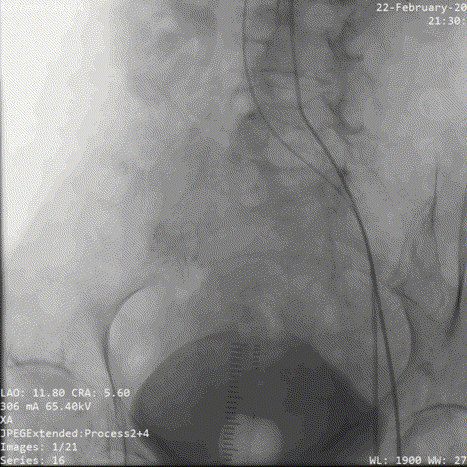

术中影像:

8.最终位置图

9.检查入路